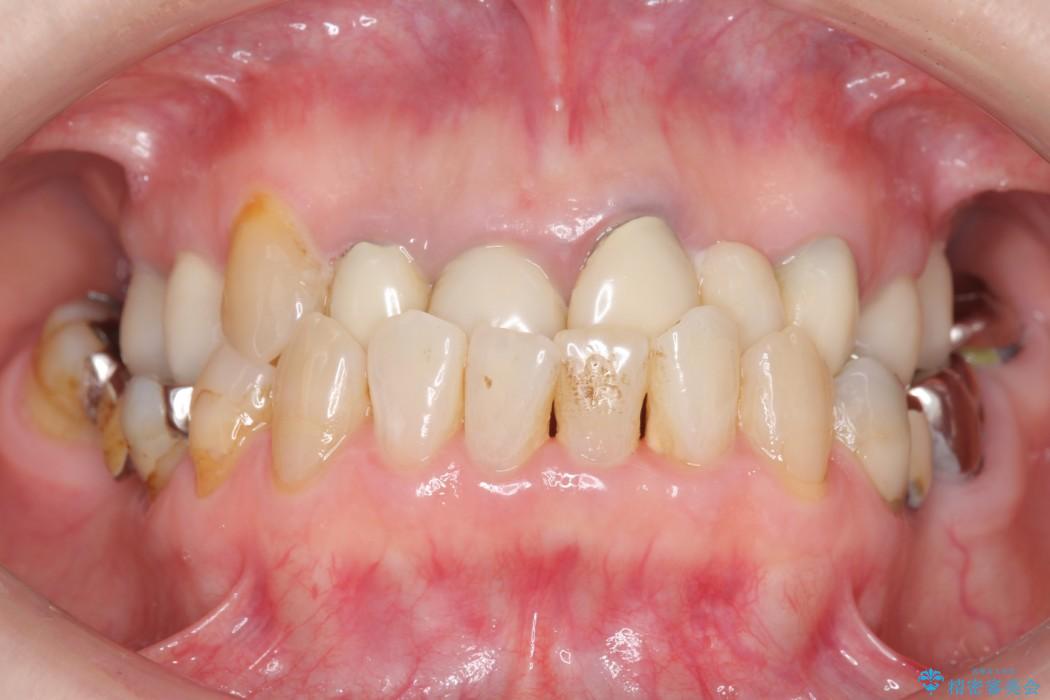

前歯のかぶせ物に関しましては、内面が金属で覆われているため歯茎にその色が透けて見えるという審美的な問題と、かぶせ物と歯の境界が不適合であるという問題がありました。

今回の症例では金属の色が透けていることを気にされていたので、土台から金属を除去し、金属を使用していないオールセラミックのかぶせ物を使用することとしました。